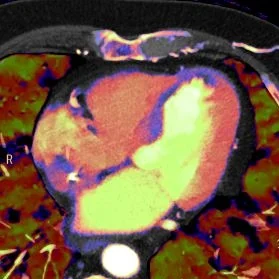

Myocardial ischemia at rest

Gopal Punjabi

October 9, 2018